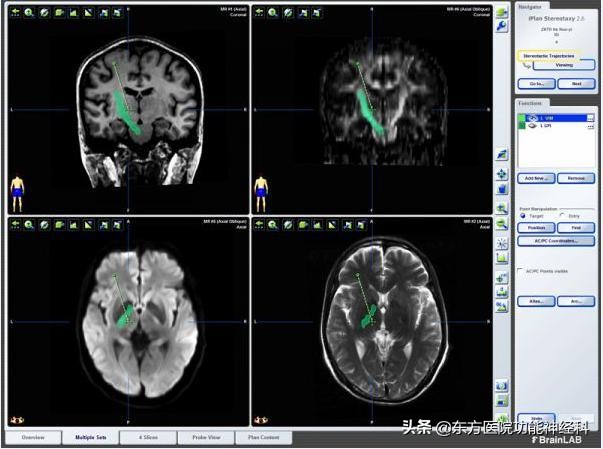

手术计划系统,通过多影像融合计算手术靶点位置及进入路径

术中将扫描图像输入计算机的立体定向手术计划系统,进行神经核团靶点的选定、校正。使用微电极记录系统不断记录植入通路的细胞电信号,进一步了解植入位置的精准程度。